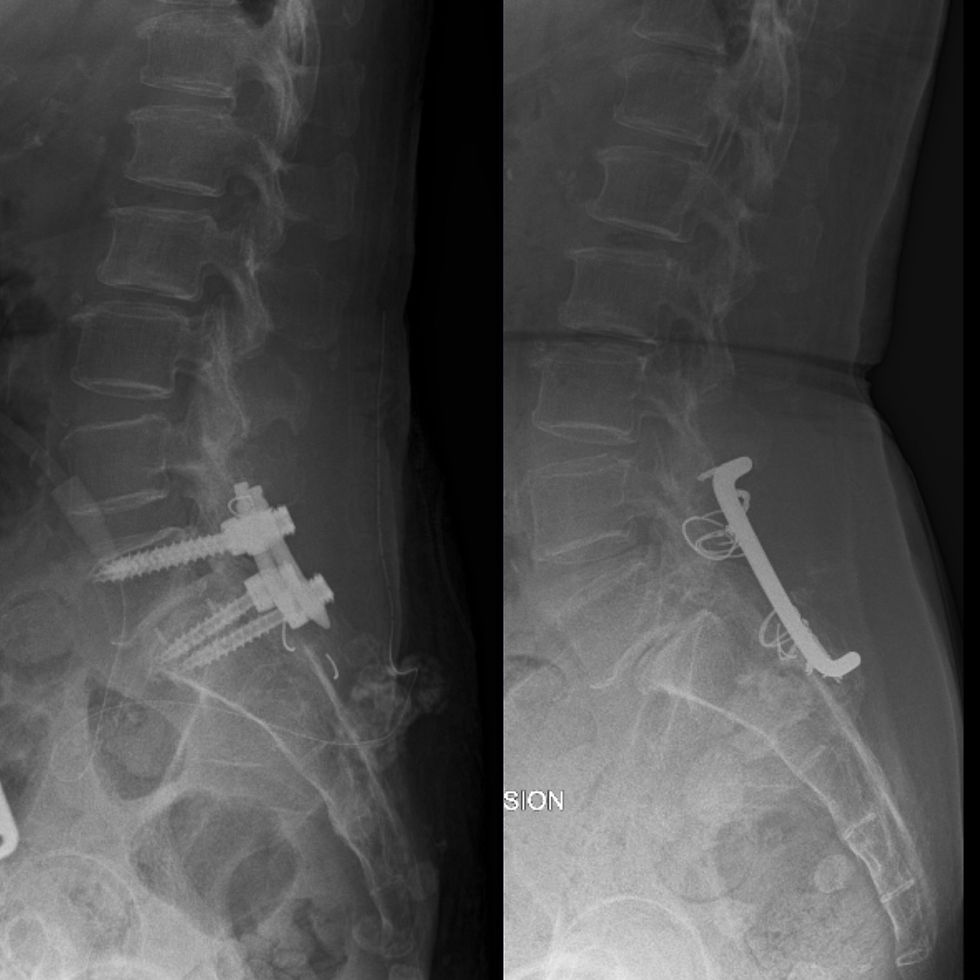

If anyone aware of needy, eligible patients requiring Orthopaedic or Spine surgery, please contact us.